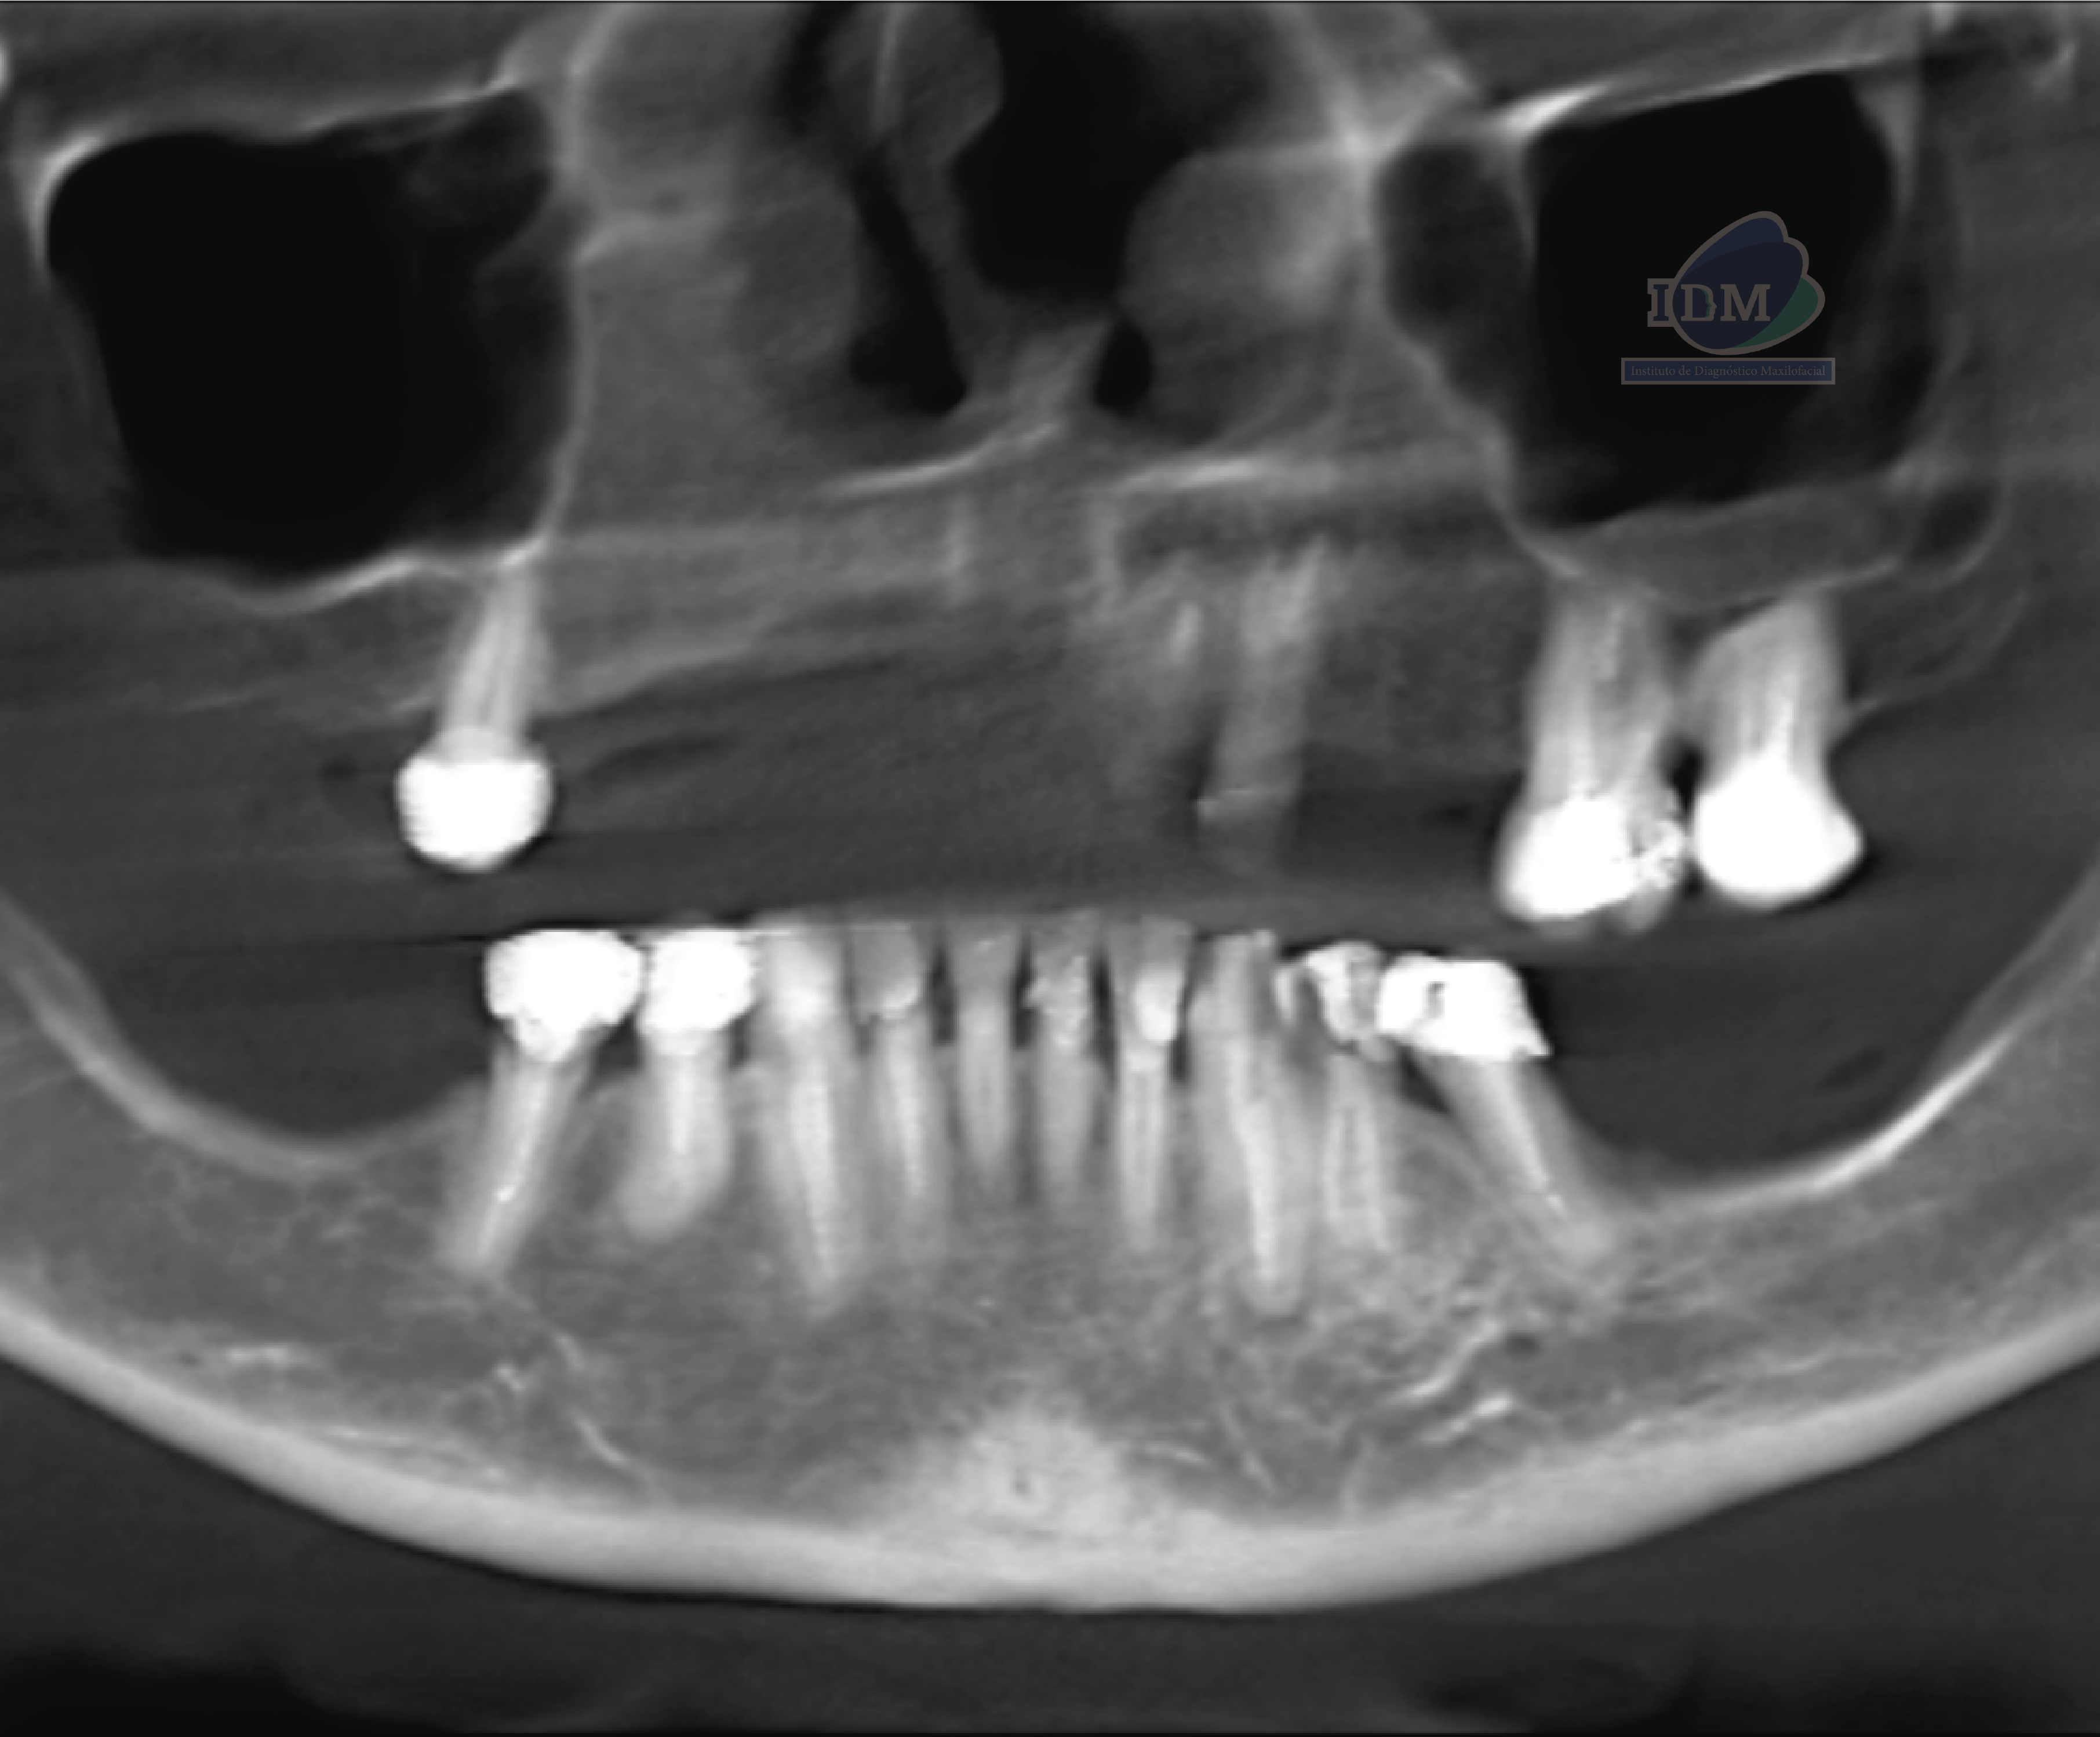

En la reformación panorámica (Figura 1), se aprecia aplanamiento de los contornos de los cóndilos mandibulares, además se observa imagen radiolúcida unilocular proyectada sobre cóndilo mandibular izquierdo, de limites definido, bordes corticalizados.

A la evaluación de la tomografía volumétrica (CBCT) de la ATM en boca cerrada, en los cortes axiales (Figura 2), coronales (Figura 3) y sagitales (Figura 4), se aprecia aplanamiento de la vertiente posterior del cóndilo mandibular del lado izquierdo con presencia de imagen hipodensa localizado próximo a la vertiente superior compatible con quiste subcondral, además se aprecia disminución de espacio articular posterior en ATM izquierda y disminución del espacio articular anterior en ATM derecha.

En las reconstrucciones 3D se representa de manera didáctica Quiste Óseo Sub Condral. (Figura 4).